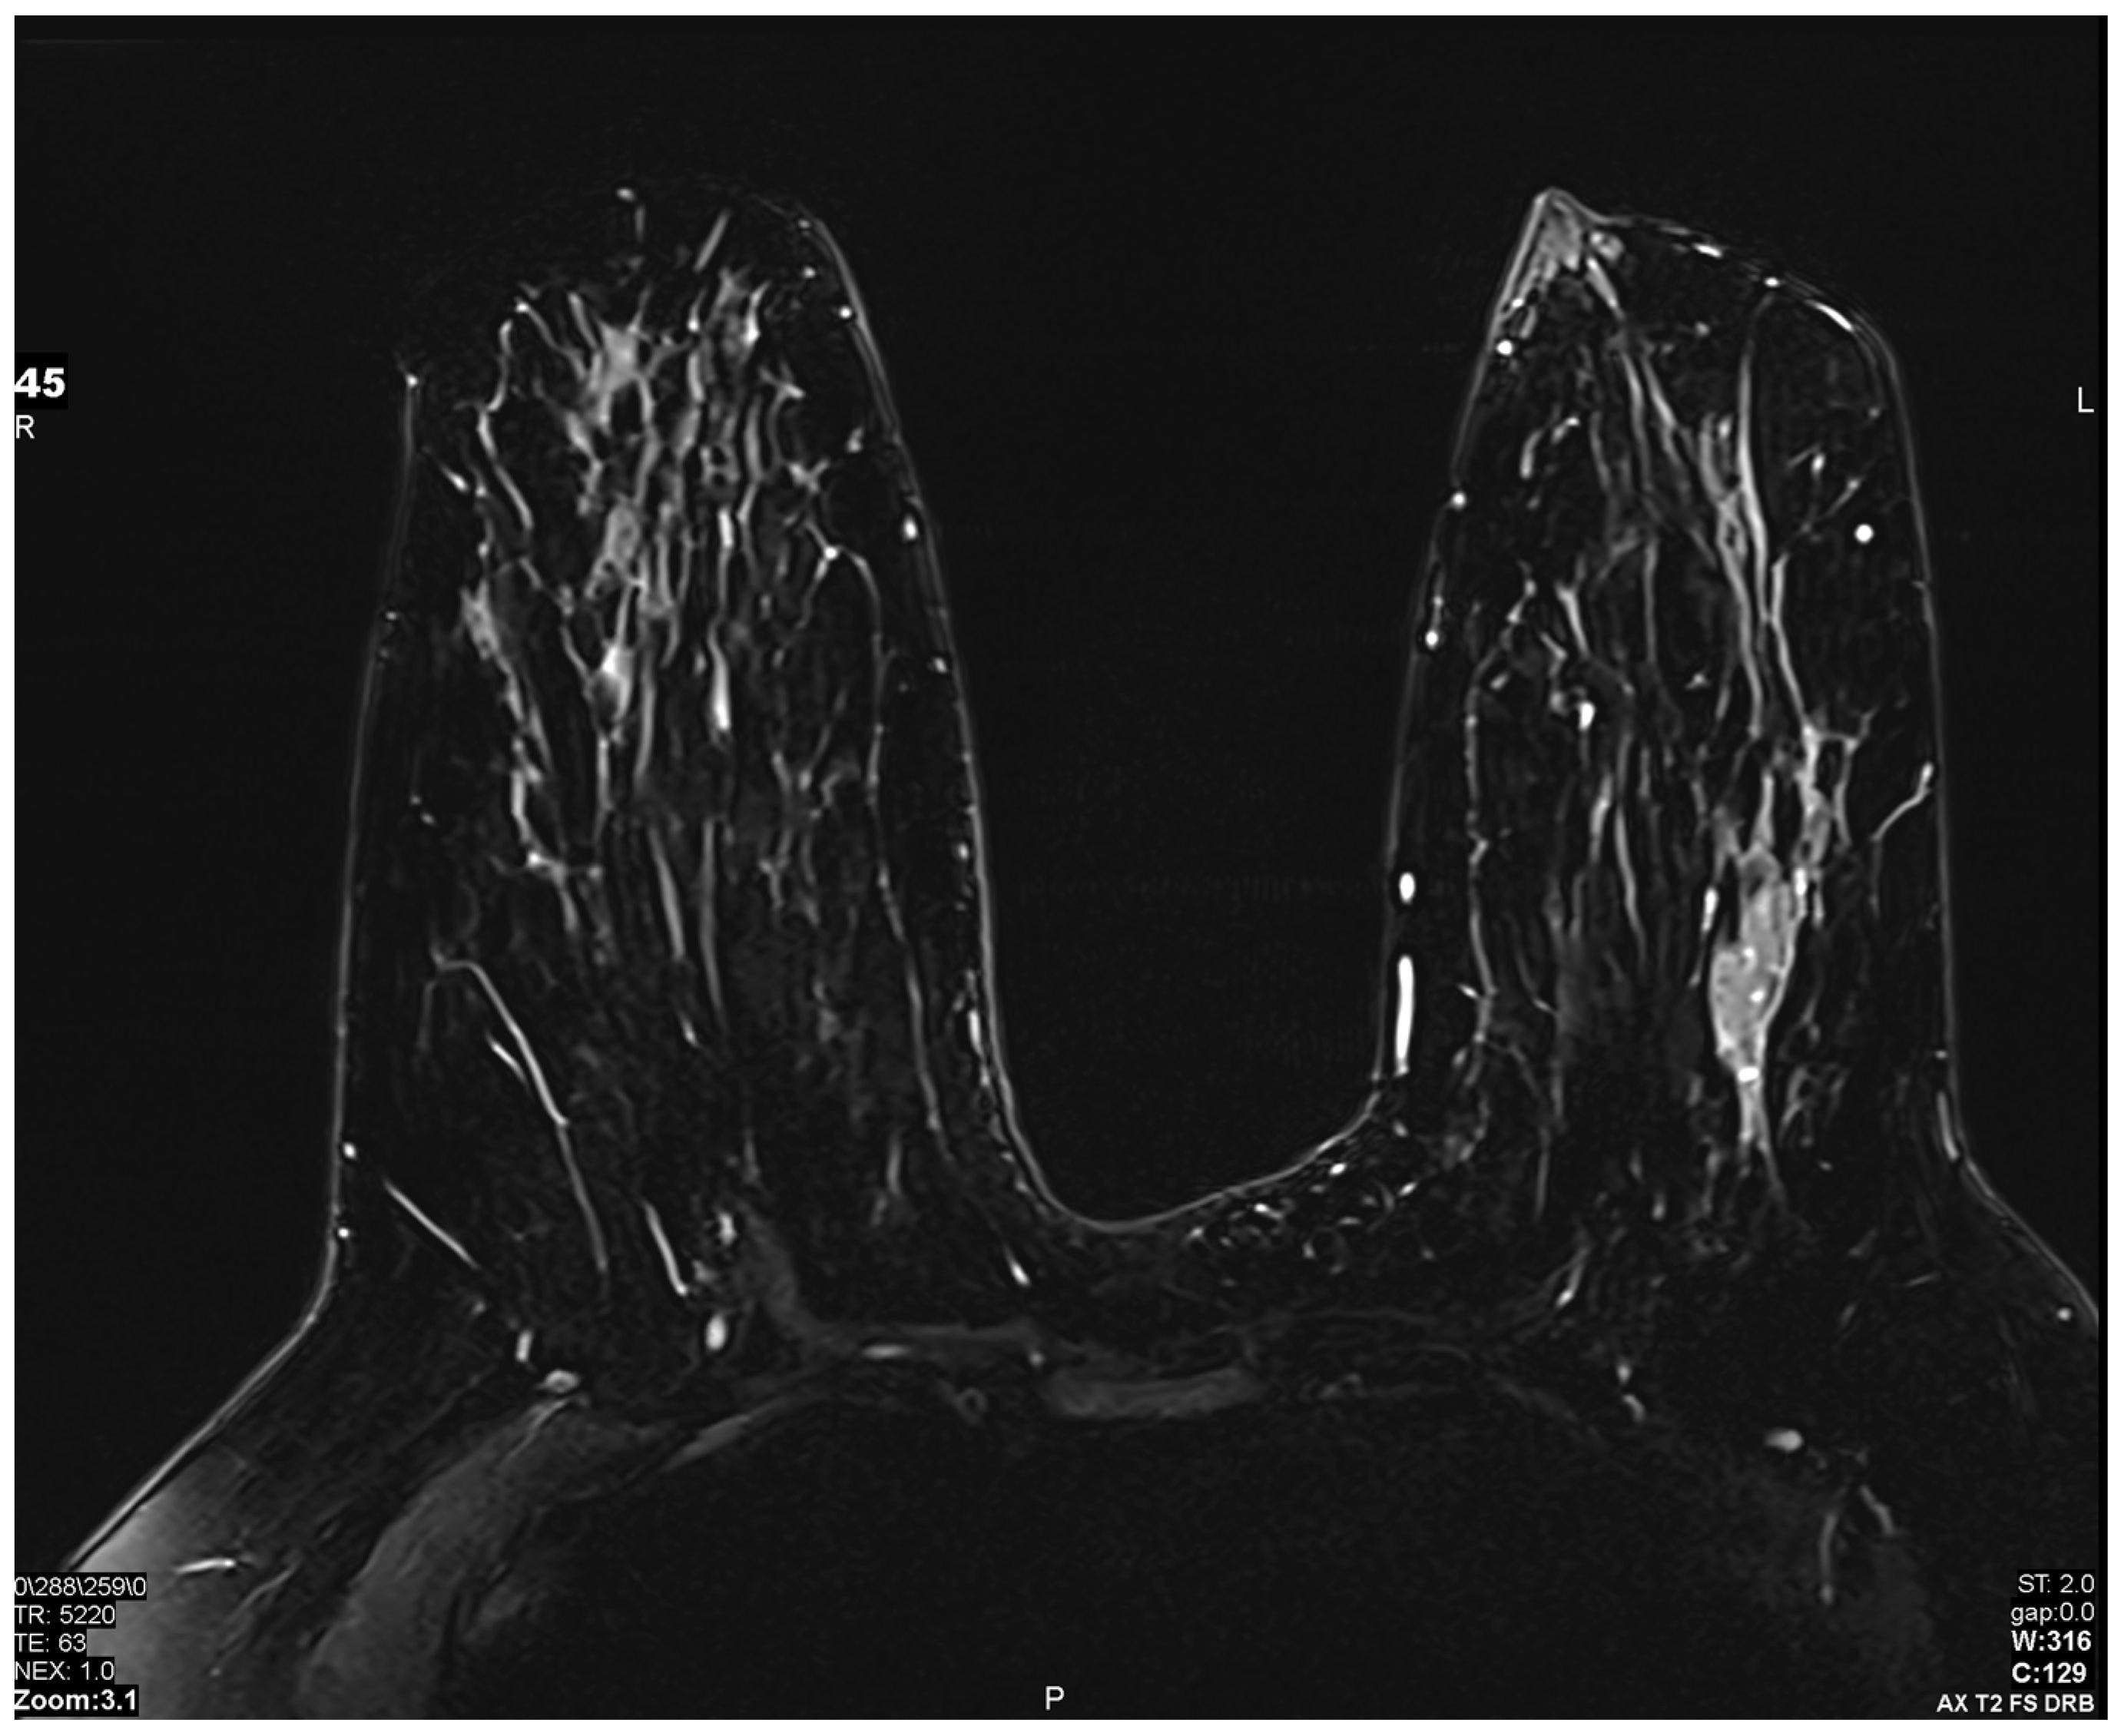

Figure 5.

Artificial intelligence (AI) sequence utilized to accelerate image acquisition time: A deep resolve boost (DRB) AI sequence was utilized to increase the signal-to-noise ratio by artificially filling k-space, allowing for accelerated image acquisition. Images obtained from the Icahn School of Medicine at Mount Sinai.